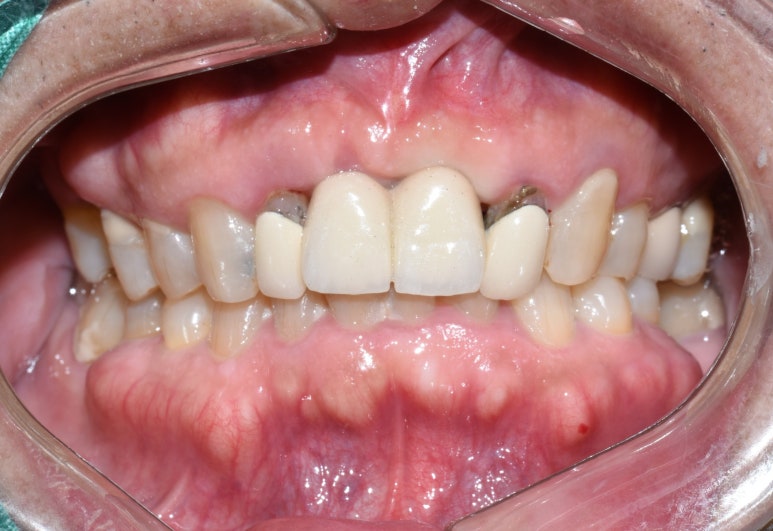

임플란트 머리부분까지 완성된 모습은 아래와 같습니다.

입안에서 자연스러운 모습을 보이고 있습니다.